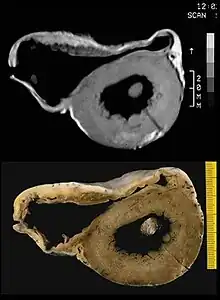

Arrhythmic cardiomyopathy pathology a) Right ventricular dilatation, anterior and posterior wall aneurysms b) transmural fibrofatty replacement c)focal subepicardial left ventricular involvement

MRI in a patient affected by ARVC/D (long axis view of the right ventricle): note the transmural diffuse bright signal in the RV free wall on spin echo T1 (a) due to massive myocardial atrophy with fatty replacement (b).

In vitro MRI and corresponding cross section of the heart in ARVD show RV dilatation with anterior and posterior aneurysms (17-year-old asymptomatic male athlete who died suddenly during a soccer game).